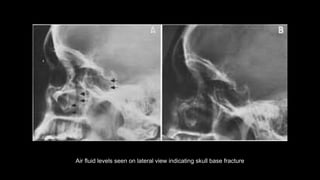

Lateral view

 It is a non angled lateral radiograph of the skull.

It provides an overview of all the sinuses.

 The sagittal midline of the patient’s head is

parallel to the image detector.

 The beam travels laterally, with 0 of

⁰

angulation, through a point 4cm above the

EAC.

• collimation

• superiorly to include skin margins

• inferiorly to include base of skull

• anteriorly to include frontal bone

• posteriorly to the skin margins

Air fluid levels seen on lateral view indicating skull base fracture

Air fluid levelsseen on lateral view indicating skull base fracture